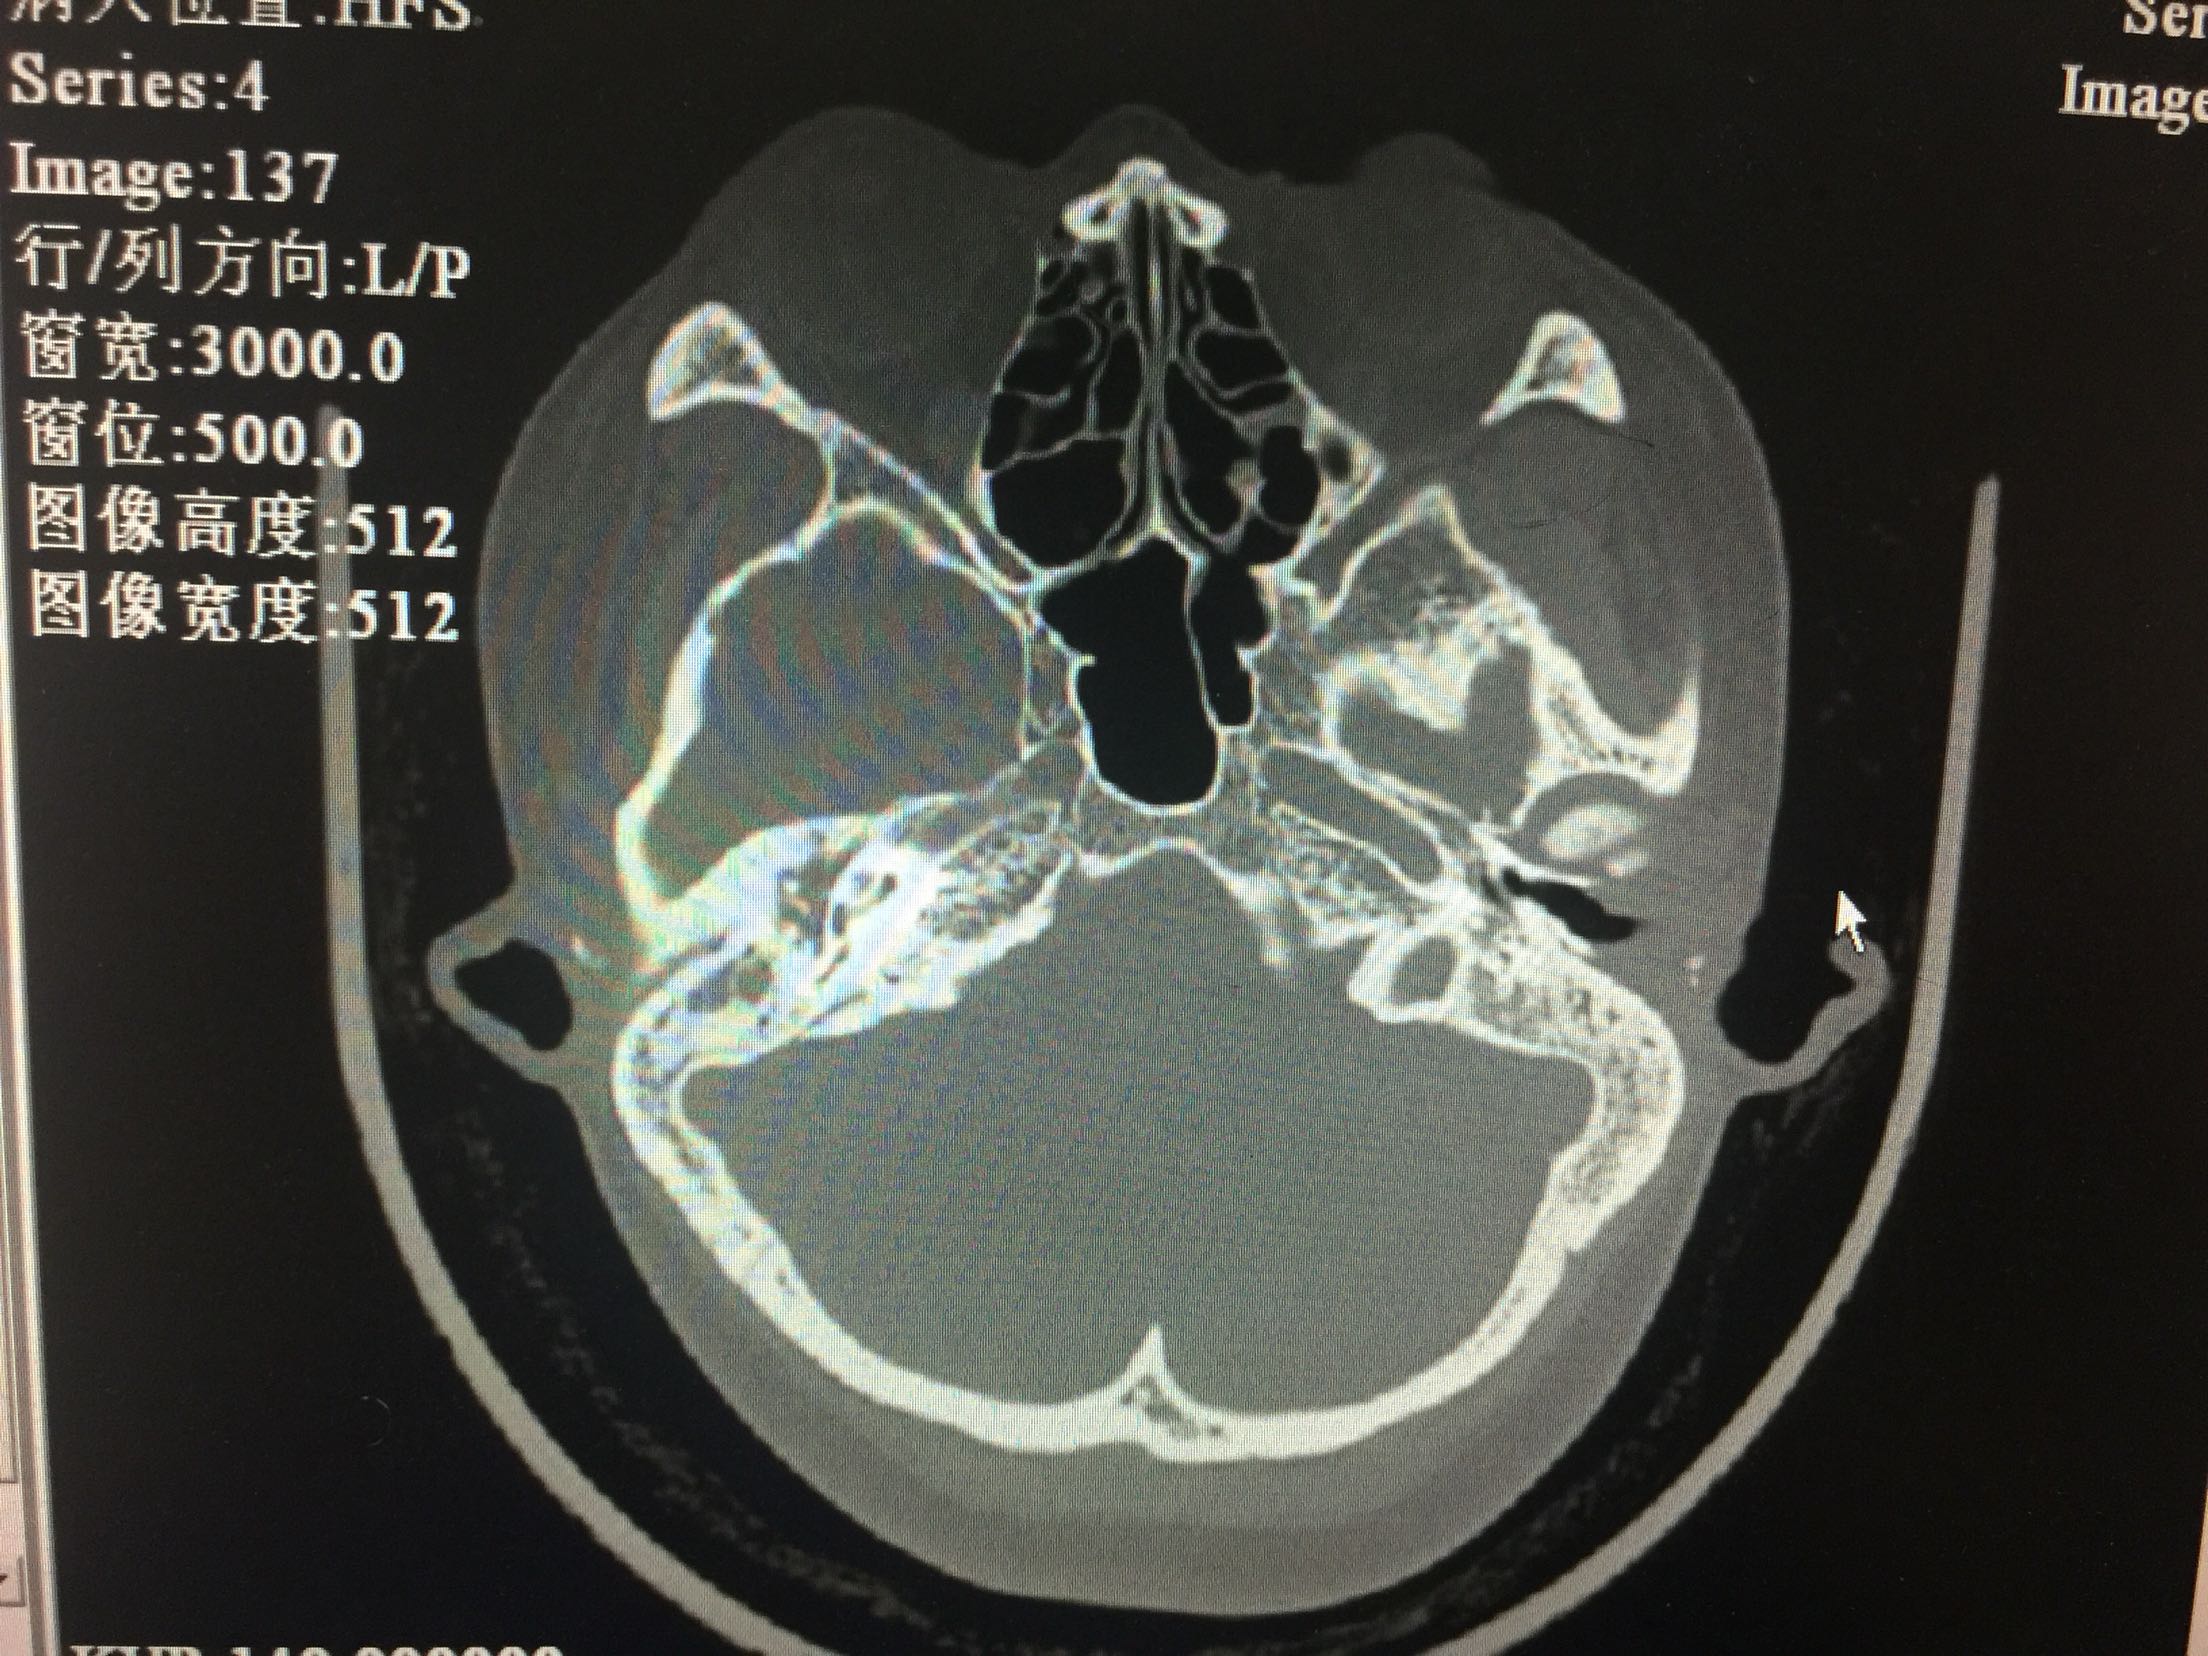

声导抗:双侧鼓室曲线B型,声反射未引出。颞骨CT:考虑双耳中耳乳突炎。

入院诊断:1.传导性聋(双)2.耳硬化症(双)?3.先天性小耳畸形(双)。治疗:入院后完善检查,全麻下行耳显微镜下左鼓室探查+骨岬开窗人工镫骨植入+外耳道成形术。左耳内切口,分离外耳道皮瓣见外耳道深部骨性狭窄,用电钻扩大外耳道,自后方完整掀开鼓膜后部。电钻磨开后鼓室,探查听骨链,见砧骨长突畸形变短,镫骨完全缺如,卵圆窗封闭,锤骨正常,锤砧关节活动好。用微钻圆窗后上相当于卵圆窗位置骨岬开窗,少量外淋巴液流出。选用合适人工听骨置于砧骨长脚上,末端植入骨岬开窗处。术后更正诊断为:1.传导性聋(双)2.先天性听骨链畸形(左)?3.先天性小耳畸形(双)。